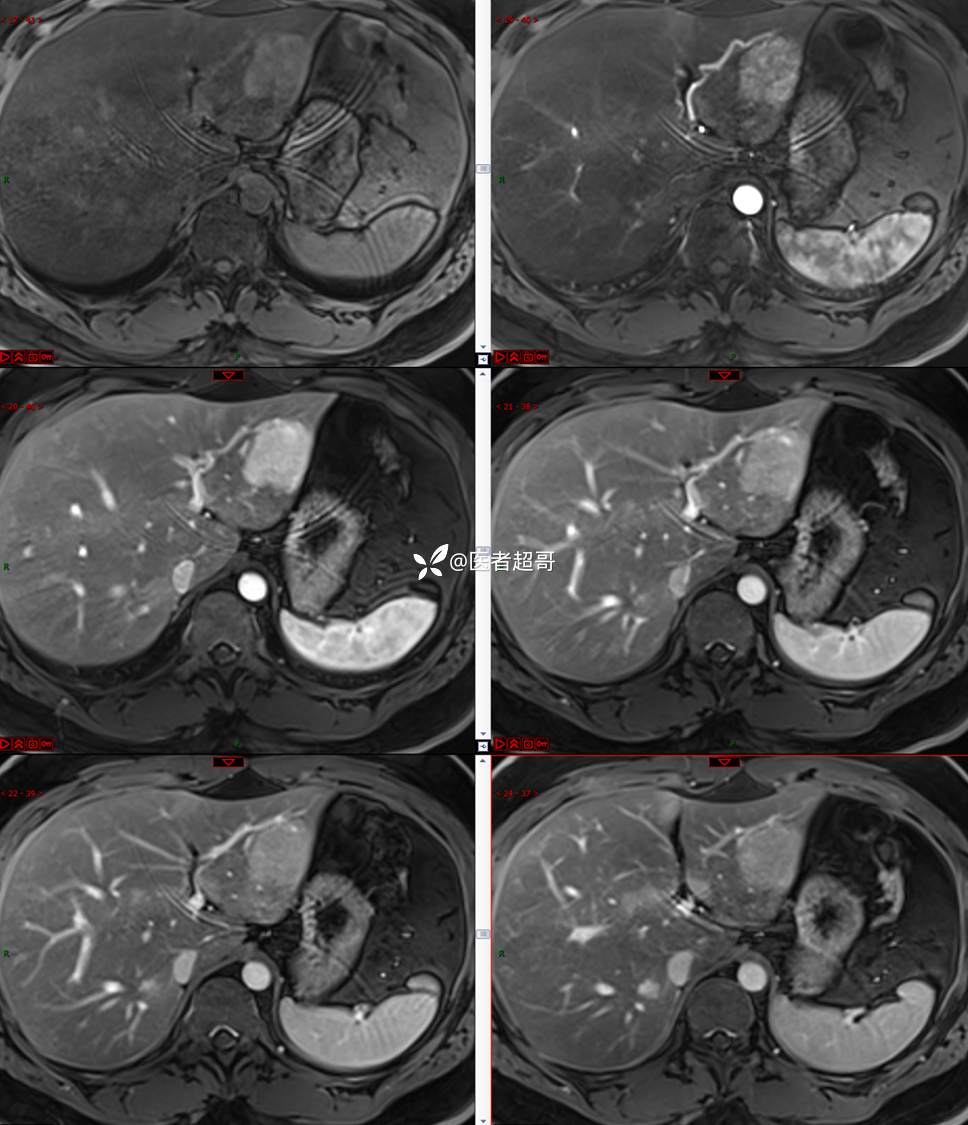

【影诊笔记685】男,31y,发现肝占位性病变5天就诊,请诊断分析,有病理结果!

主 诉:发现肝占位性病变5天。

现病史:患者缘于5天前体检时发现肝占位性病变,未予以特殊处置。现患者为求系统诊治就诊于我院,行普美显提示:肝左叶富血供占位,请结合临床及其他检查,肝多发血管瘤,脂肪肝,肝囊肿,请结合临床。门诊以“肝占位性病变”收入我科。病程中,饮食睡眠可,二便可,近期体重未见明显变化。